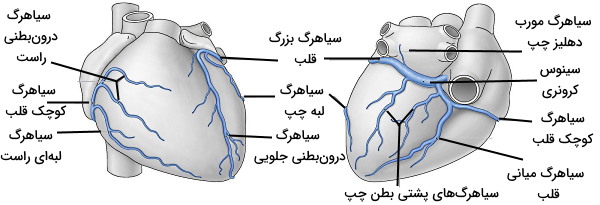

خون این رگها پس از تبادل اکسیژن و مواد غذایی با بافت قلبی بهوسیله سینوس کرونری (سیاهرگ سطح پشتی قلب) از میوکارد به دهلیز راست منتقل میشود. سیروس کرونری خون با غلظت پایین اکسیژن را از چهار شاخه اصلی دریافت میکند.

- سیاهرگ بزرگ قلب: این سیاهرگ بزرگترین شاخه سینوس کرونری است که از نوک قلب شروع شده و و در سطح پشتی قلب بالا میرود. سپس قطر آن افزایش یافته و سینوس کرونری را تشکیل میدهد.

- سیاهرگ کوچک قلب: این رگ در سطح جلویی قلب و در شیار بین دهلیز و بطن راست قرار دارد.

- سیاهرگ میانی قلب: این سیاهرگ از نوک قلب شروع میشود و در شیار بینبطنی پشتی بالا میرود.

- سیاهرگ پشتی قلب: این سیاهرگ در سطح پشتی بطن چپ و سمت چپ سیاهرگ میانی قلب قرار دارد.